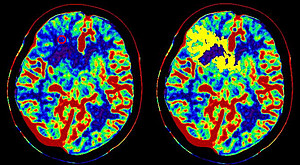

Biomedical Imaging for the Diagnosis of Alzheimer''s disease